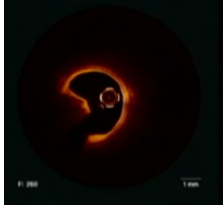

Nieves Gonzalo博士还指出,本例患者进行了长期随访数据显示(如图8、9)Shockwave IVL治疗后支架可持续地保持很好的膨胀程度,且血管壁内膜光滑,血管愈合更充分。

图片

8

图9